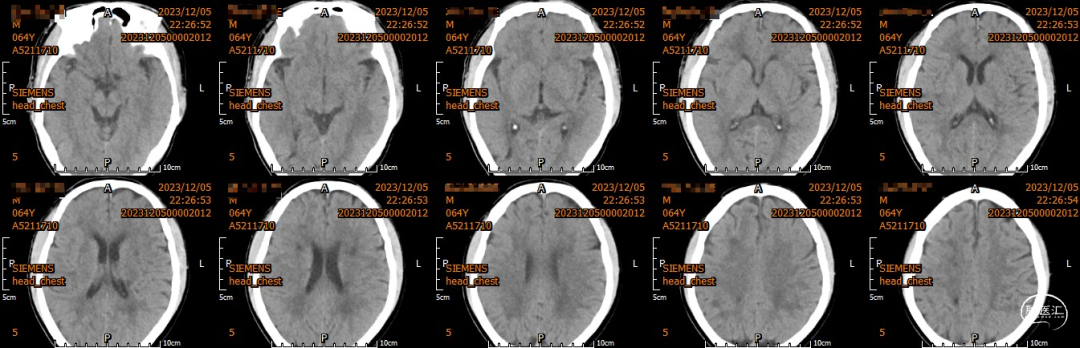

颅脑CT示:

1.双侧侧脑室旁及右侧额顶叶多发脑梗死;

2.脑白质变性。